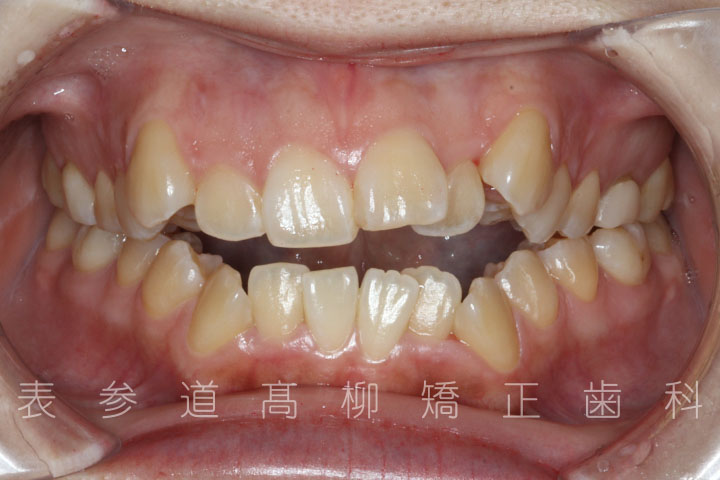

前歯のガタガタ感と開咬でお悩みの患者様の症例をご紹介いたします。

・前歯部開咬

・上下前歯部叢生(凸凹歯並び)

術前術後の比較